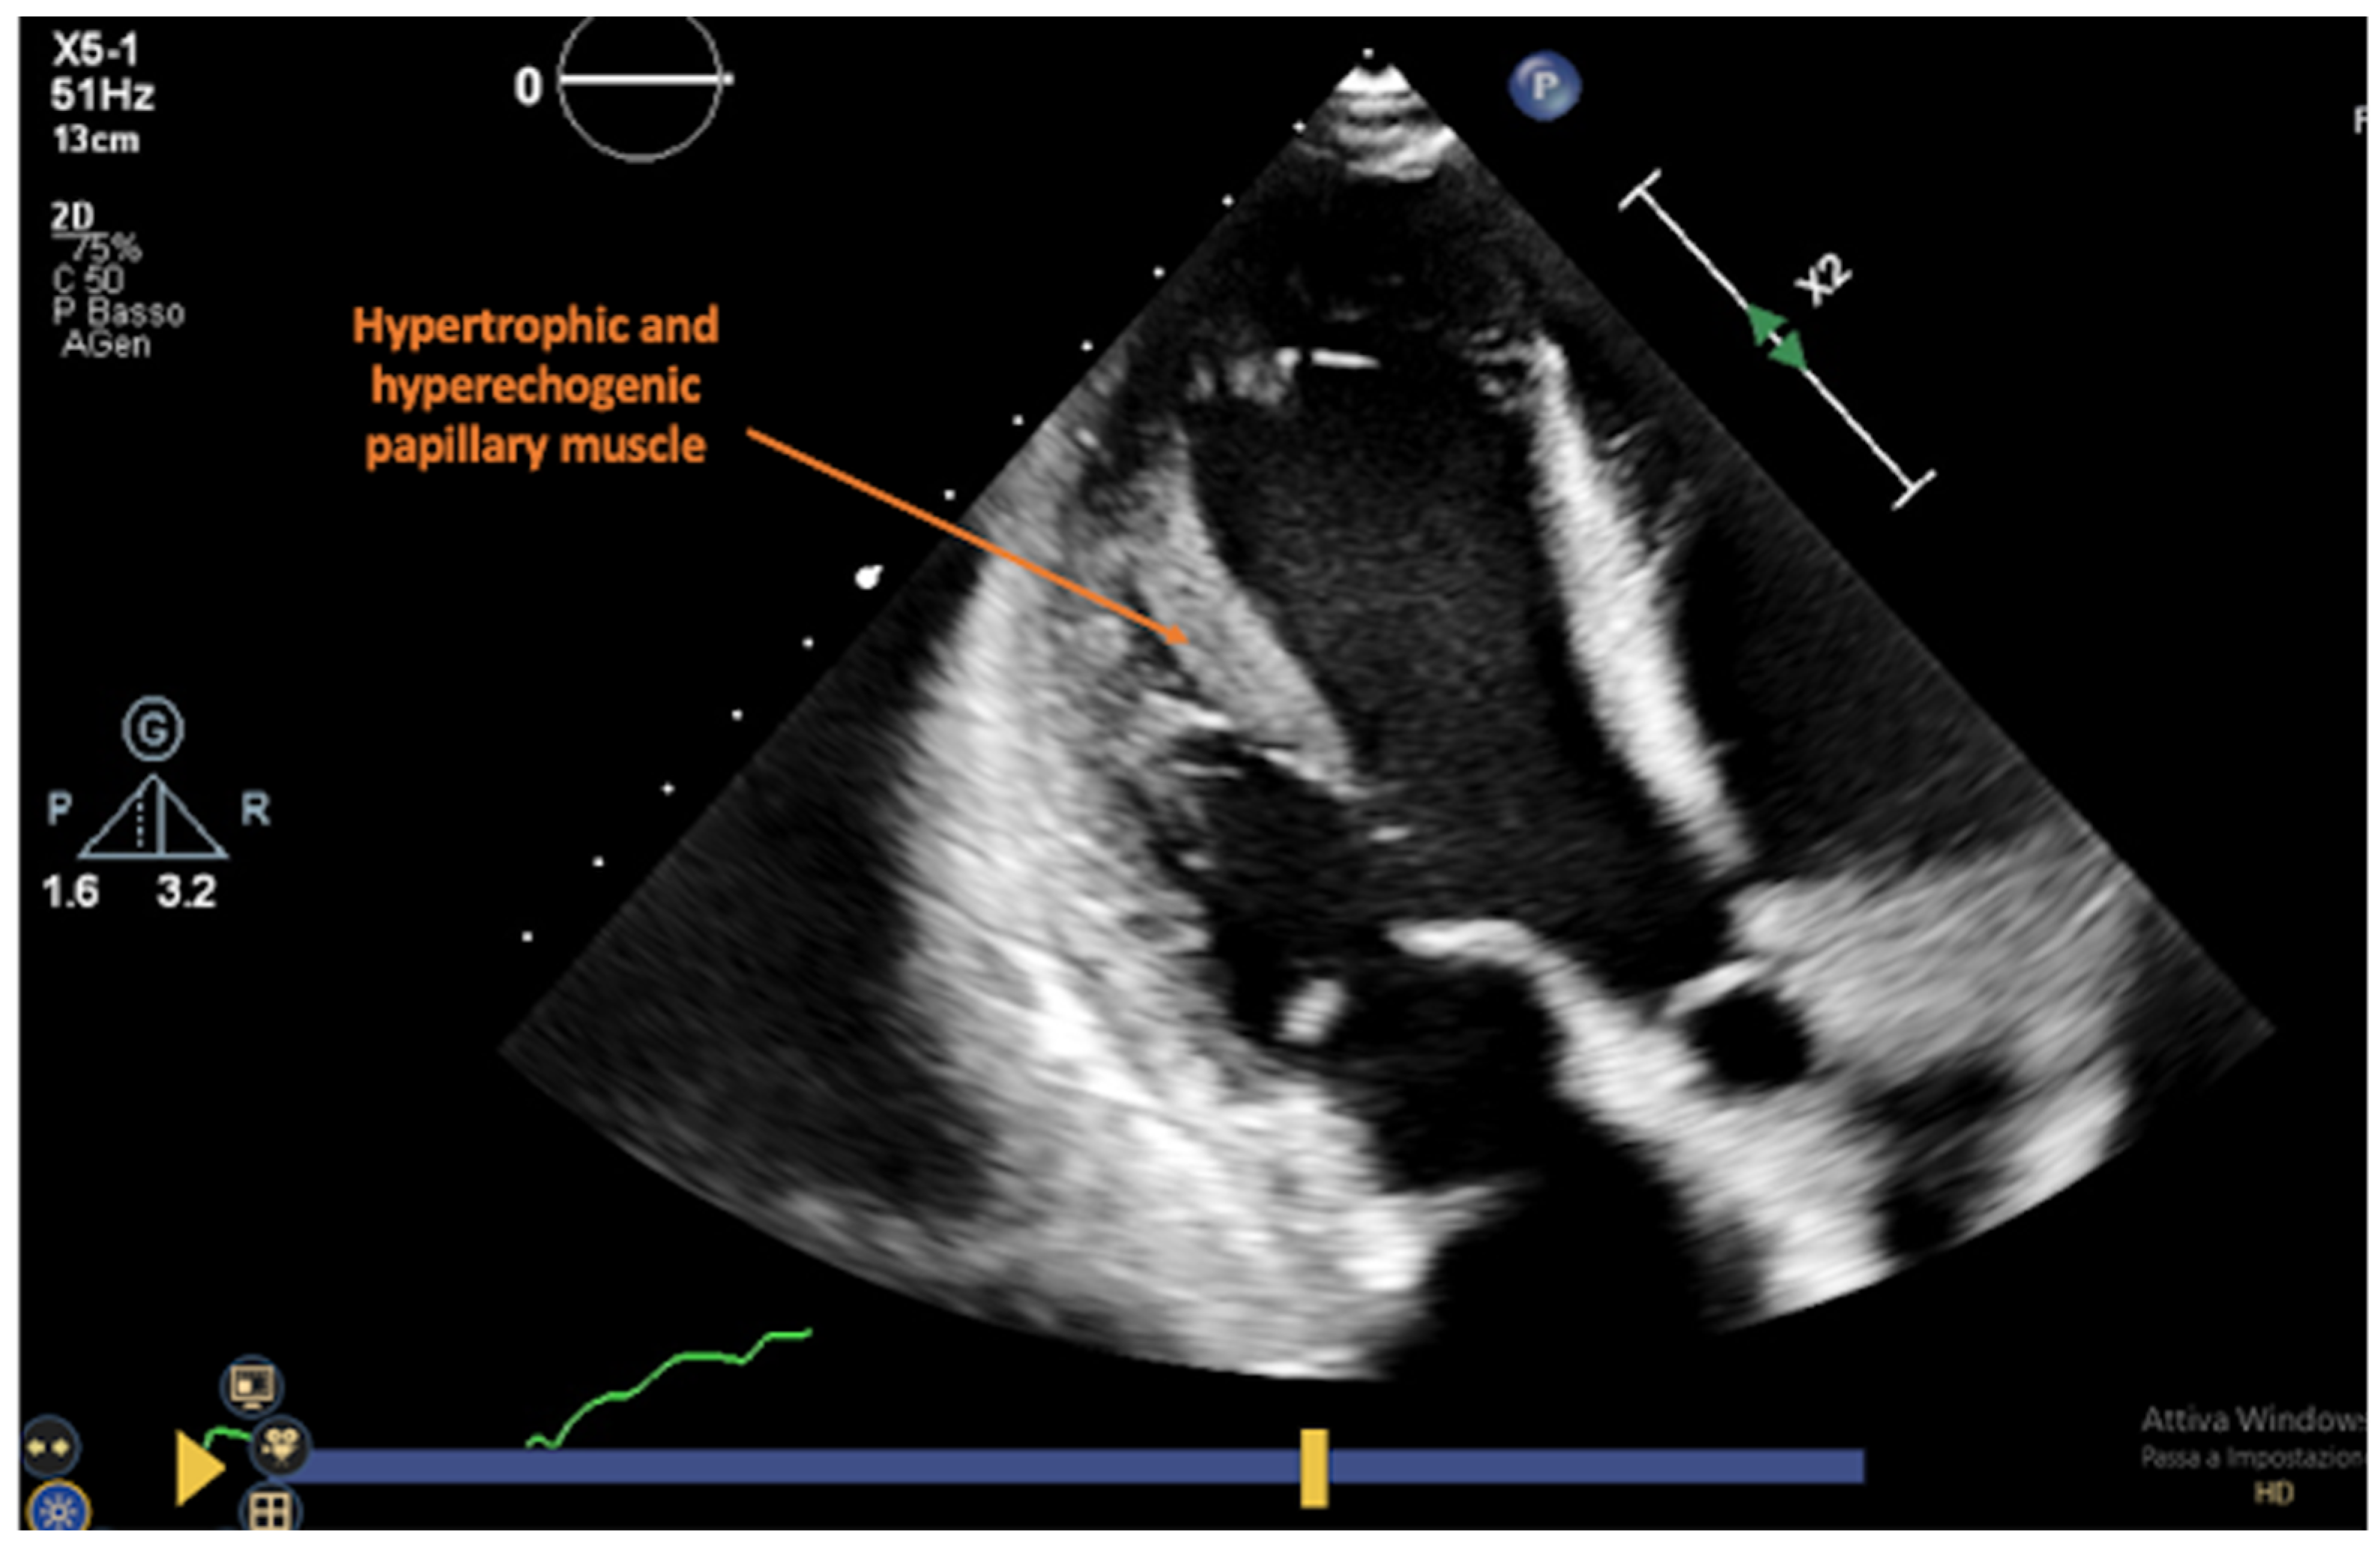

3. Primary Graft Dysfunction

4. Echocardiography in Graft Rejection